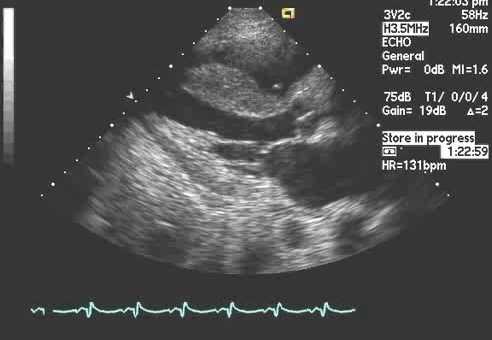

Проведение эхокардиографии

Никакой особой сложности подготовка к эхокардиографии не вызывает. Необходимо раздеться до пояса и улечься на кушетку на левый бок. Подобная поза способствует сближению левой стороны грудной клетки и верхушки сердца. Это, в свою очередь, дает более качественную картинку сердца с четырехкамерной позиции.

Далее гелем мажется район грудной клетки, куда крепятся датчики. Их различные позиции позволяют наглядно видеть все отделы сердца и осуществить измерения с фиксацией показателей работы и размеров. Датчики, подключаемые к эхокардиографу, не причиняют боли или дискомфорта. Ультразвуковые колебания от датчиков передаются в человеческое тело. Акустические волны двигаются в тканях и видоизменяются, а затем возвращаются к датчику. Здесь происходит их преобразование в электросигналы, которые и обрабатываются эхокардиографом. Изменение волн связано с переменами в состоянии внутренних органов. Именно в этом заключается отличие Эхо КГ от ЭКГ (электрокардиограммы), демонстрирующей графическую запись активности сердца, а не его строения.

Полученные результаты отображаются на экране в виде четкой картинки. Описанный метод обследования является наиболее распространенным и носит название «трансторакальная эхокардиография» (от лат. «thorax» - грудная клетка), обозначающий доступ к сердцу через поверхность тела пациента. Врач, исследующий сердце человека, при таком положении пациента сидит слева или справа от него, управляет настройками аппарата в зависимости от выводимого на дисплей изображения.